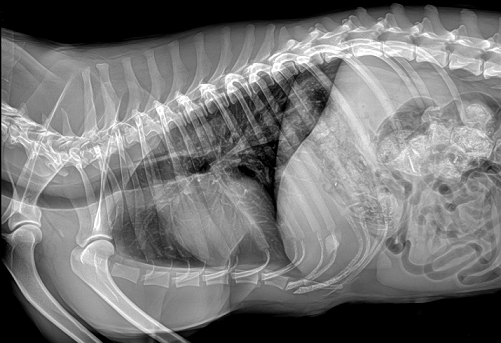

寵物DR是現(xiàn)在大多寵物醫(yī)院必備的醫(yī)療器械,它要比以往的X光更高科技一點兒:更清晰、易保存。寵物DR主要用于給寵物做X光檢查,在寵物不會說話和不用做手術(shù)的情況下,檢查寵物身體內(nèi)是否有異物、骨折、炎癥和腫瘤等常見疾病。目前市面上好的寵物DR能令動物影像成像迅速而清晰??墒菓?yīng)該如何選擇寵物DR就成為了頭疼的問題。

國產(chǎn)品牌普愛醫(yī)療寵物DR采用非晶硅平板探測器,可以令動物影像成像清晰而快速,基本上5s左右就能使動物影像清楚成像且無拖尾現(xiàn)象,而且分辨率高,極限空間分辨率可達到5.0Lp/mm;

普愛醫(yī)療寵物DR拍攝的高清照片

同時,寵物影像成像尺寸較大,成像尺寸可達43cm x 43cm,并且以DICOM格式儲存數(shù)據(jù),極大的方便了醫(yī)療工作者們追蹤檢查時使用。同時還支持窗寬、窗位、放大、旋轉(zhuǎn)、正像和負像轉(zhuǎn)換等顯示功能。